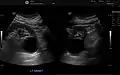

Numerous renal cysts are seen in the cystic kidney diseases, which include polycystic kidney disease and medullary sponge kidney.